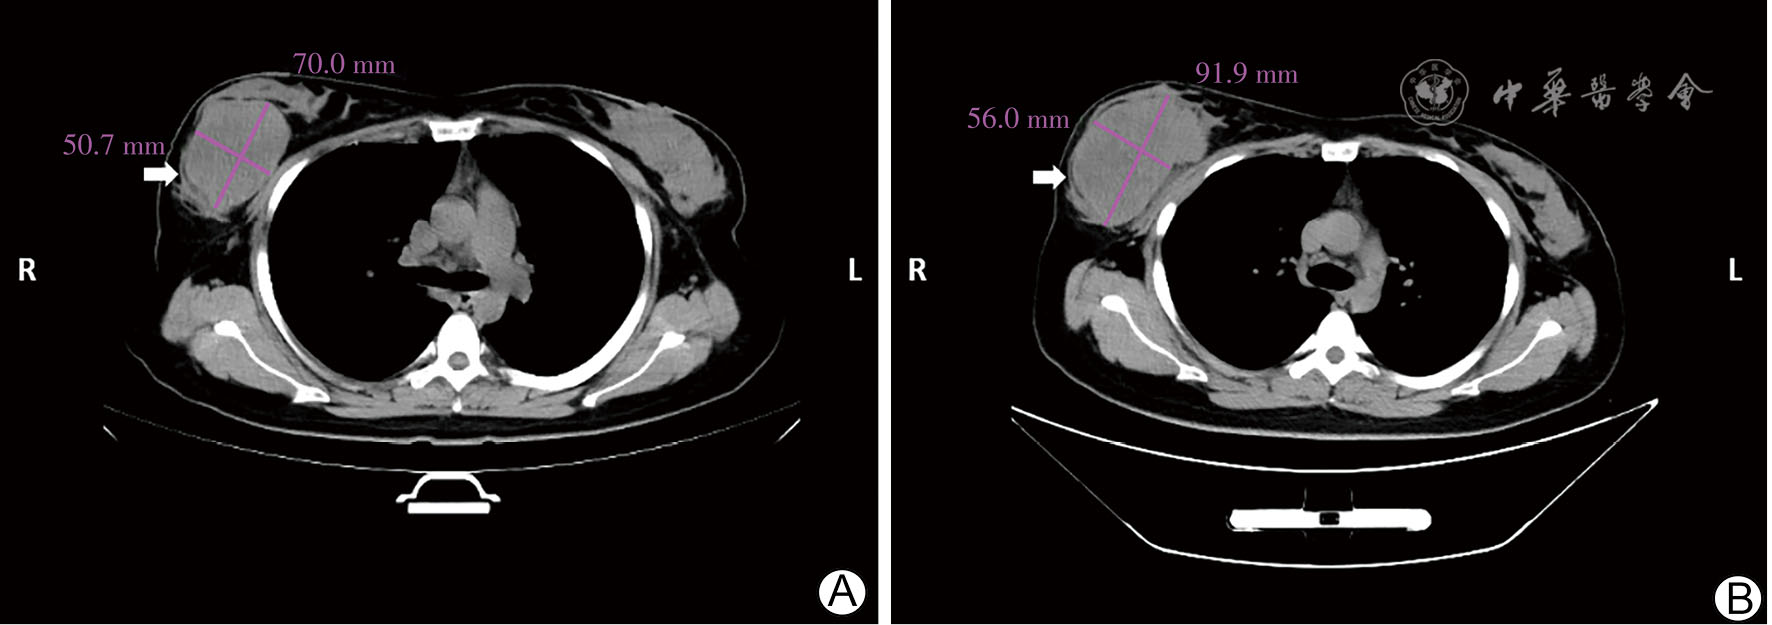

图2 三阴性乳腺癌患者新辅助化疗中断保肝治疗期间与术前右乳肿瘤胸部CT表现 A图为保肝治疗期间;B图为术前,可见右乳肿块较前明显增大 注:箭头示右乳肿瘤

图3 三阴性乳腺癌患者新辅助化疗中断保肝治疗期间与术前胸肌间淋巴结胸部CT表现 A图为保肝治疗期间;B图为术前,可见右侧腋窝胸肌间淋巴结较前增大 注:箭头示右侧腋窝胸肌间淋巴结